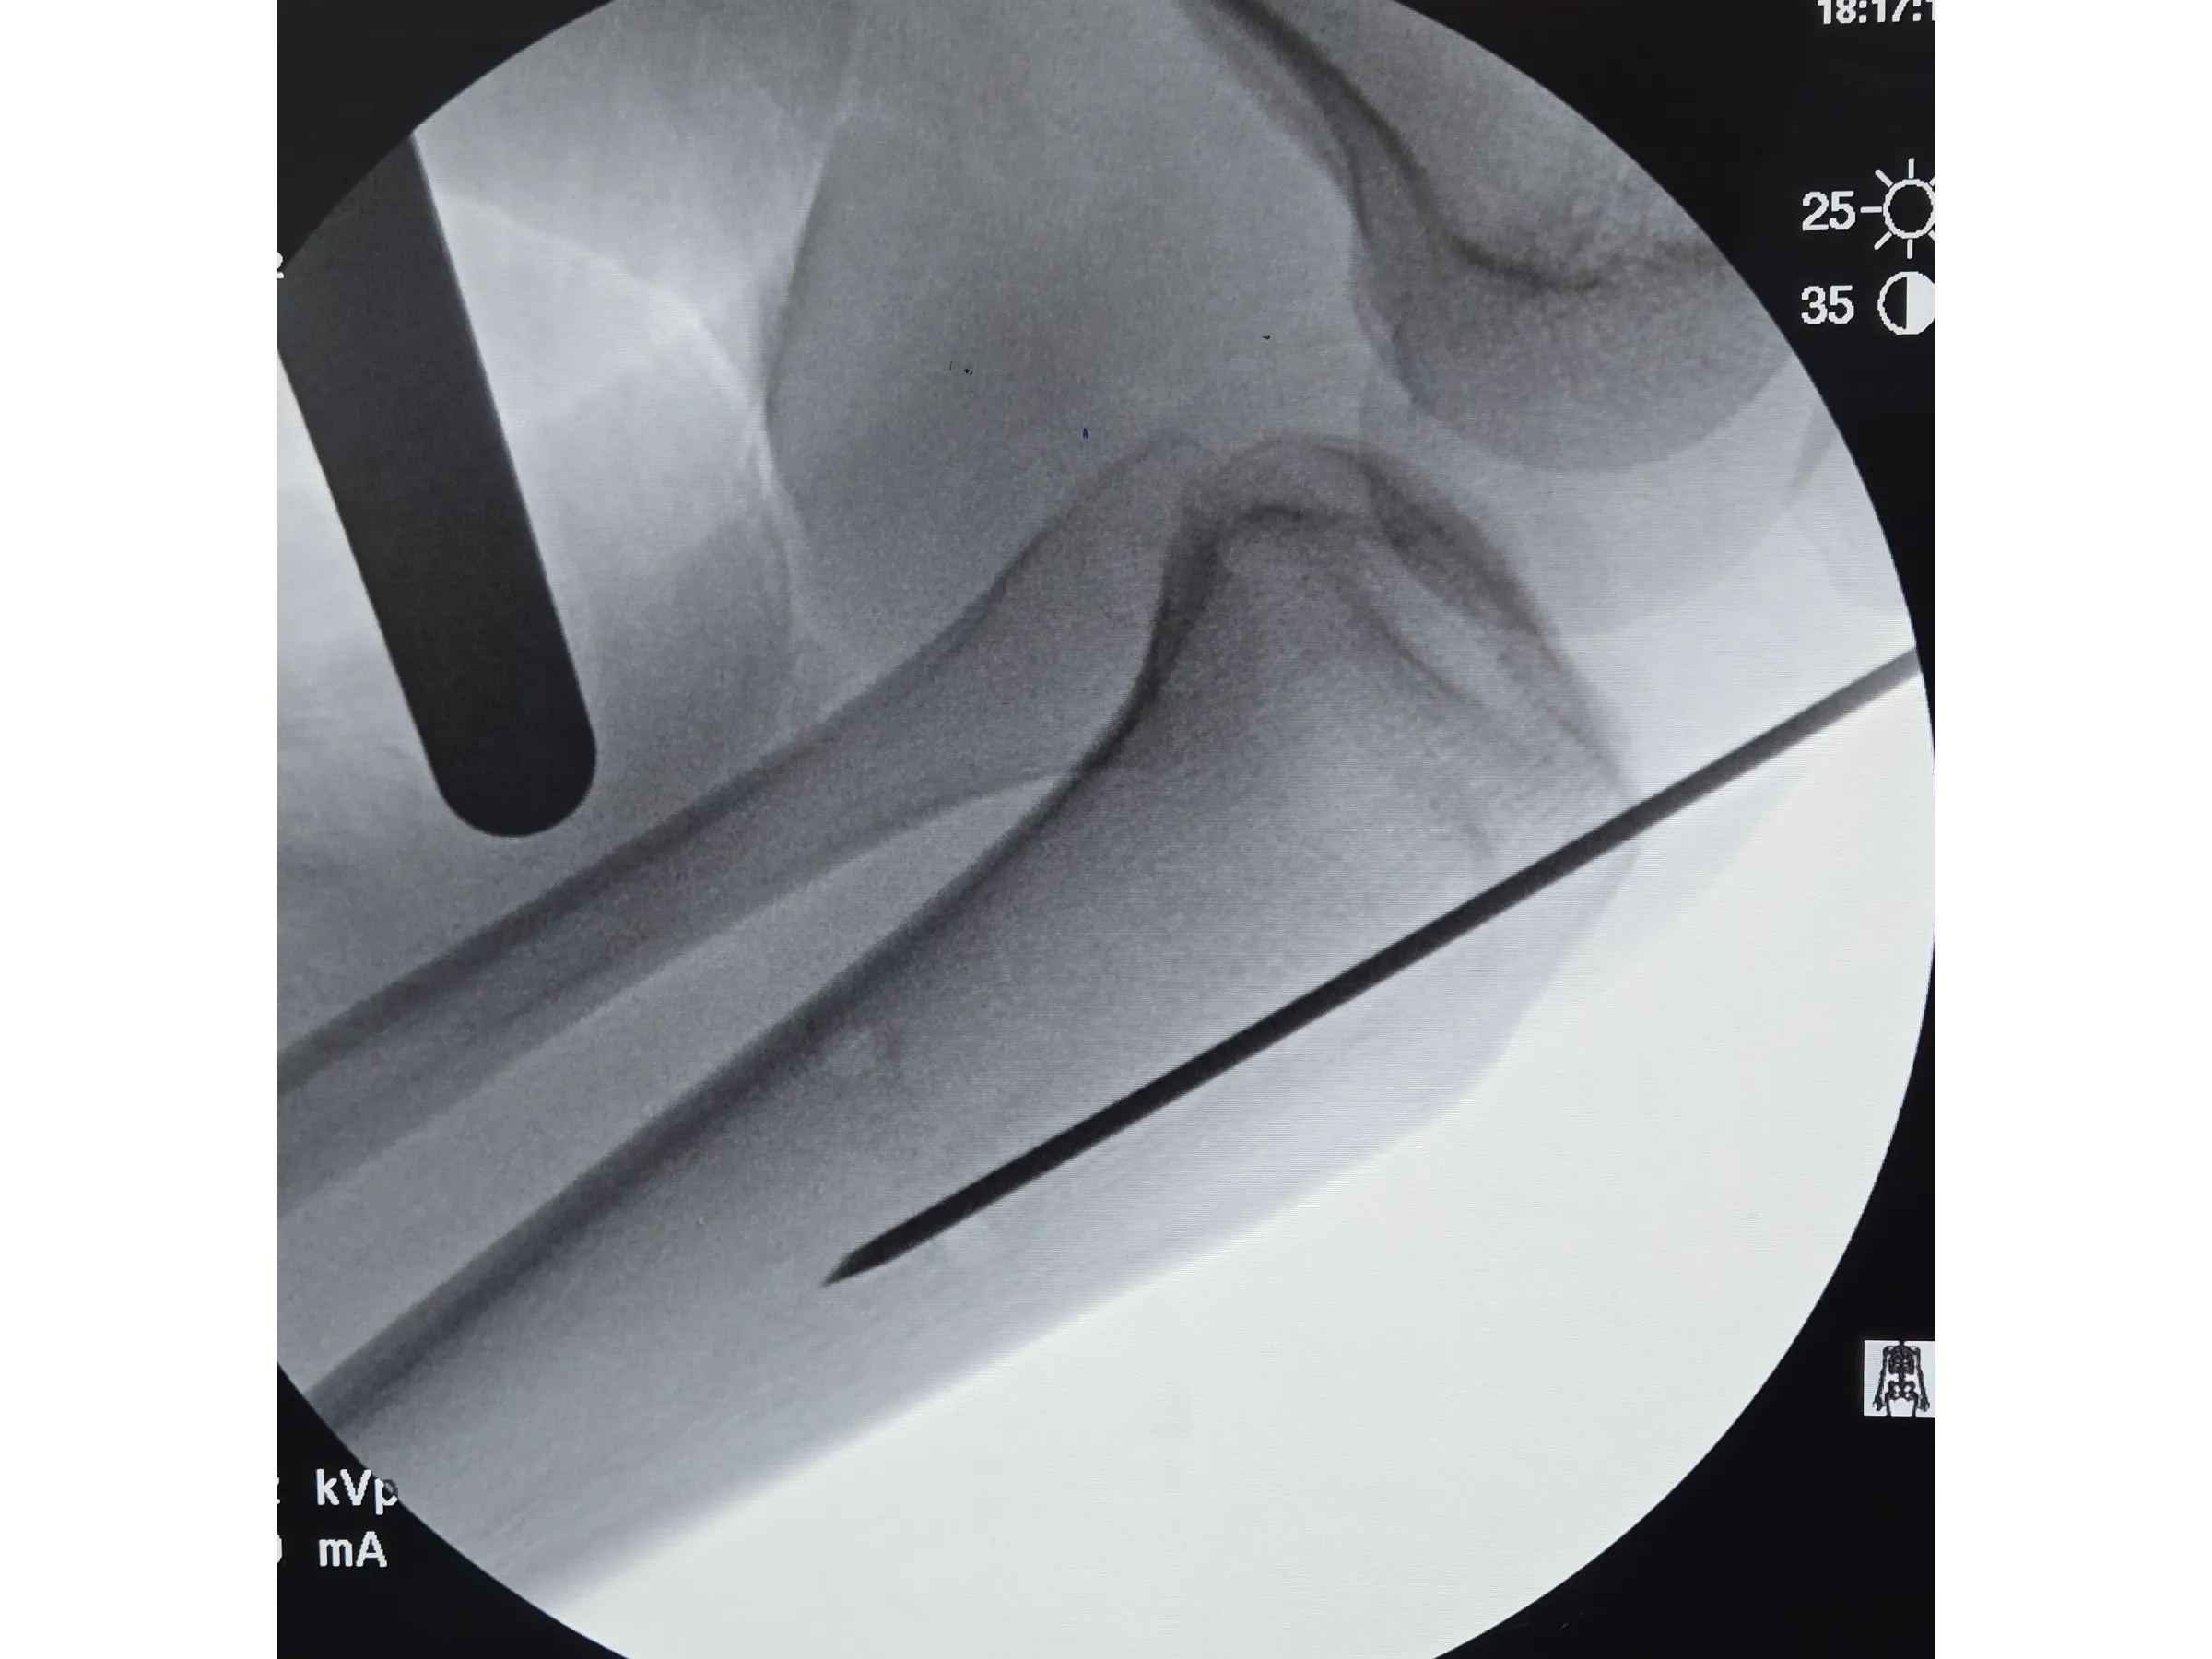

- Introdução segura do fio-guia e fio olivado com controle radiográfico;

- Controle Radiográfico Eficiente: Métodos para evitar direcionamento posterior do fio-guia e garantir centralização do fio olivado;